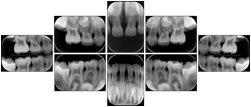

3. A dental provider wishes to capture a series of DICOM IO images for the patient’s dentition. The tooth morphology, teeth are divided into molars, premolars, canines and incisors, and a number of images for each jaw. The anatomic information was captured utilizing the triplet of schema. This standard code sequence is based on ISO 3950-2010, Dentistry - Designation system for teeth and areas of the oral cavity.

Every IO image should have anatomic information either through the primary or modifier sequence.

In most standard cases, images are oriented in structured layouts. These structured displays are useful to be shared between providers for reference purposes.

Table OO.1.1-1 shows structured display standard templates, where Viewset ID is based on the Japanese Society for Oral and Maxillofacial Radiology (JSOMR) classification provided by JIRA (Japan Medical Imaging and Radiological Systems Industries Association, www.jira-net.or.jp). Expected or typical teeth to be imaged location, region and designation codes are based on ISO 3950-2010, Dentistry - Designation system for teeth and areas of the oral cavity. For all the hanging protocols listed in OO.1.1-1, the value to use for Hanging Protocol Creator (0072,0008) is "JSOMR" and the value to use for Hanging Protocol Name (0072,0002) does not include "JSOMR" (e.g., "DL-S001A", not "JSOMR DL-S001A").